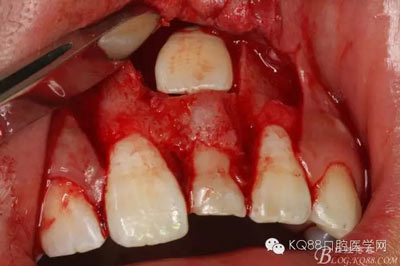

圖11.掀開(kāi)骨壁。摘除牙瘤及牙囊組織

圖12.摘除囊壁后,暴露出21的切端

圖13.超聲骨刀清理周?chē)M織,21有Ⅰ°松動(dòng)